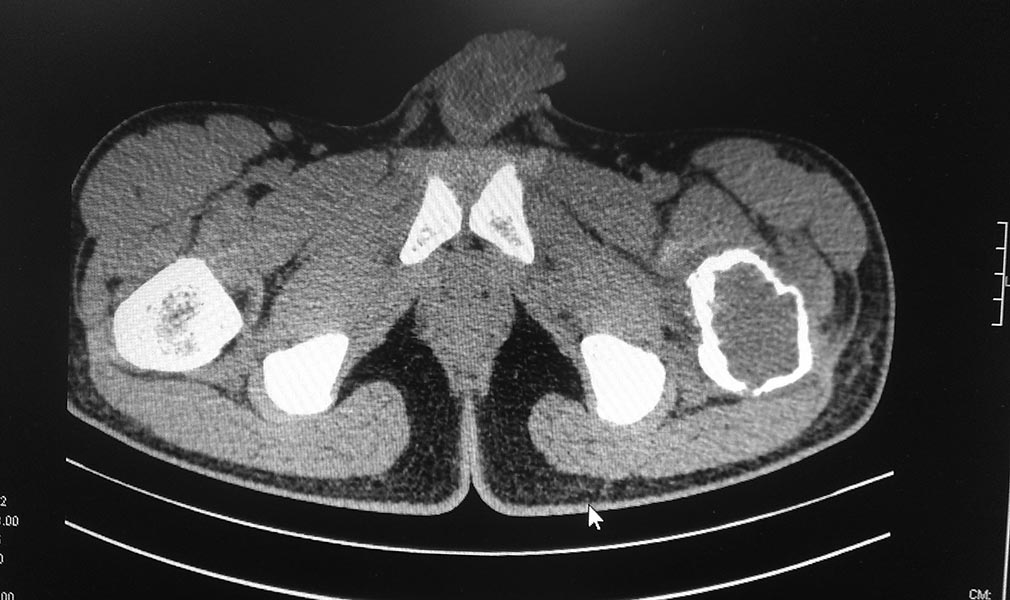

кисте. Пациенту произведено КТ обеих тазобедренных суставов.

Заключение: КТ - признаки объемного образования области шейки и большого

вертела левой бедренной кости дифференцировать с фиброзной дисплазией.

Сростающийся патологический чрезвертельный перелом левой бедренной кости.